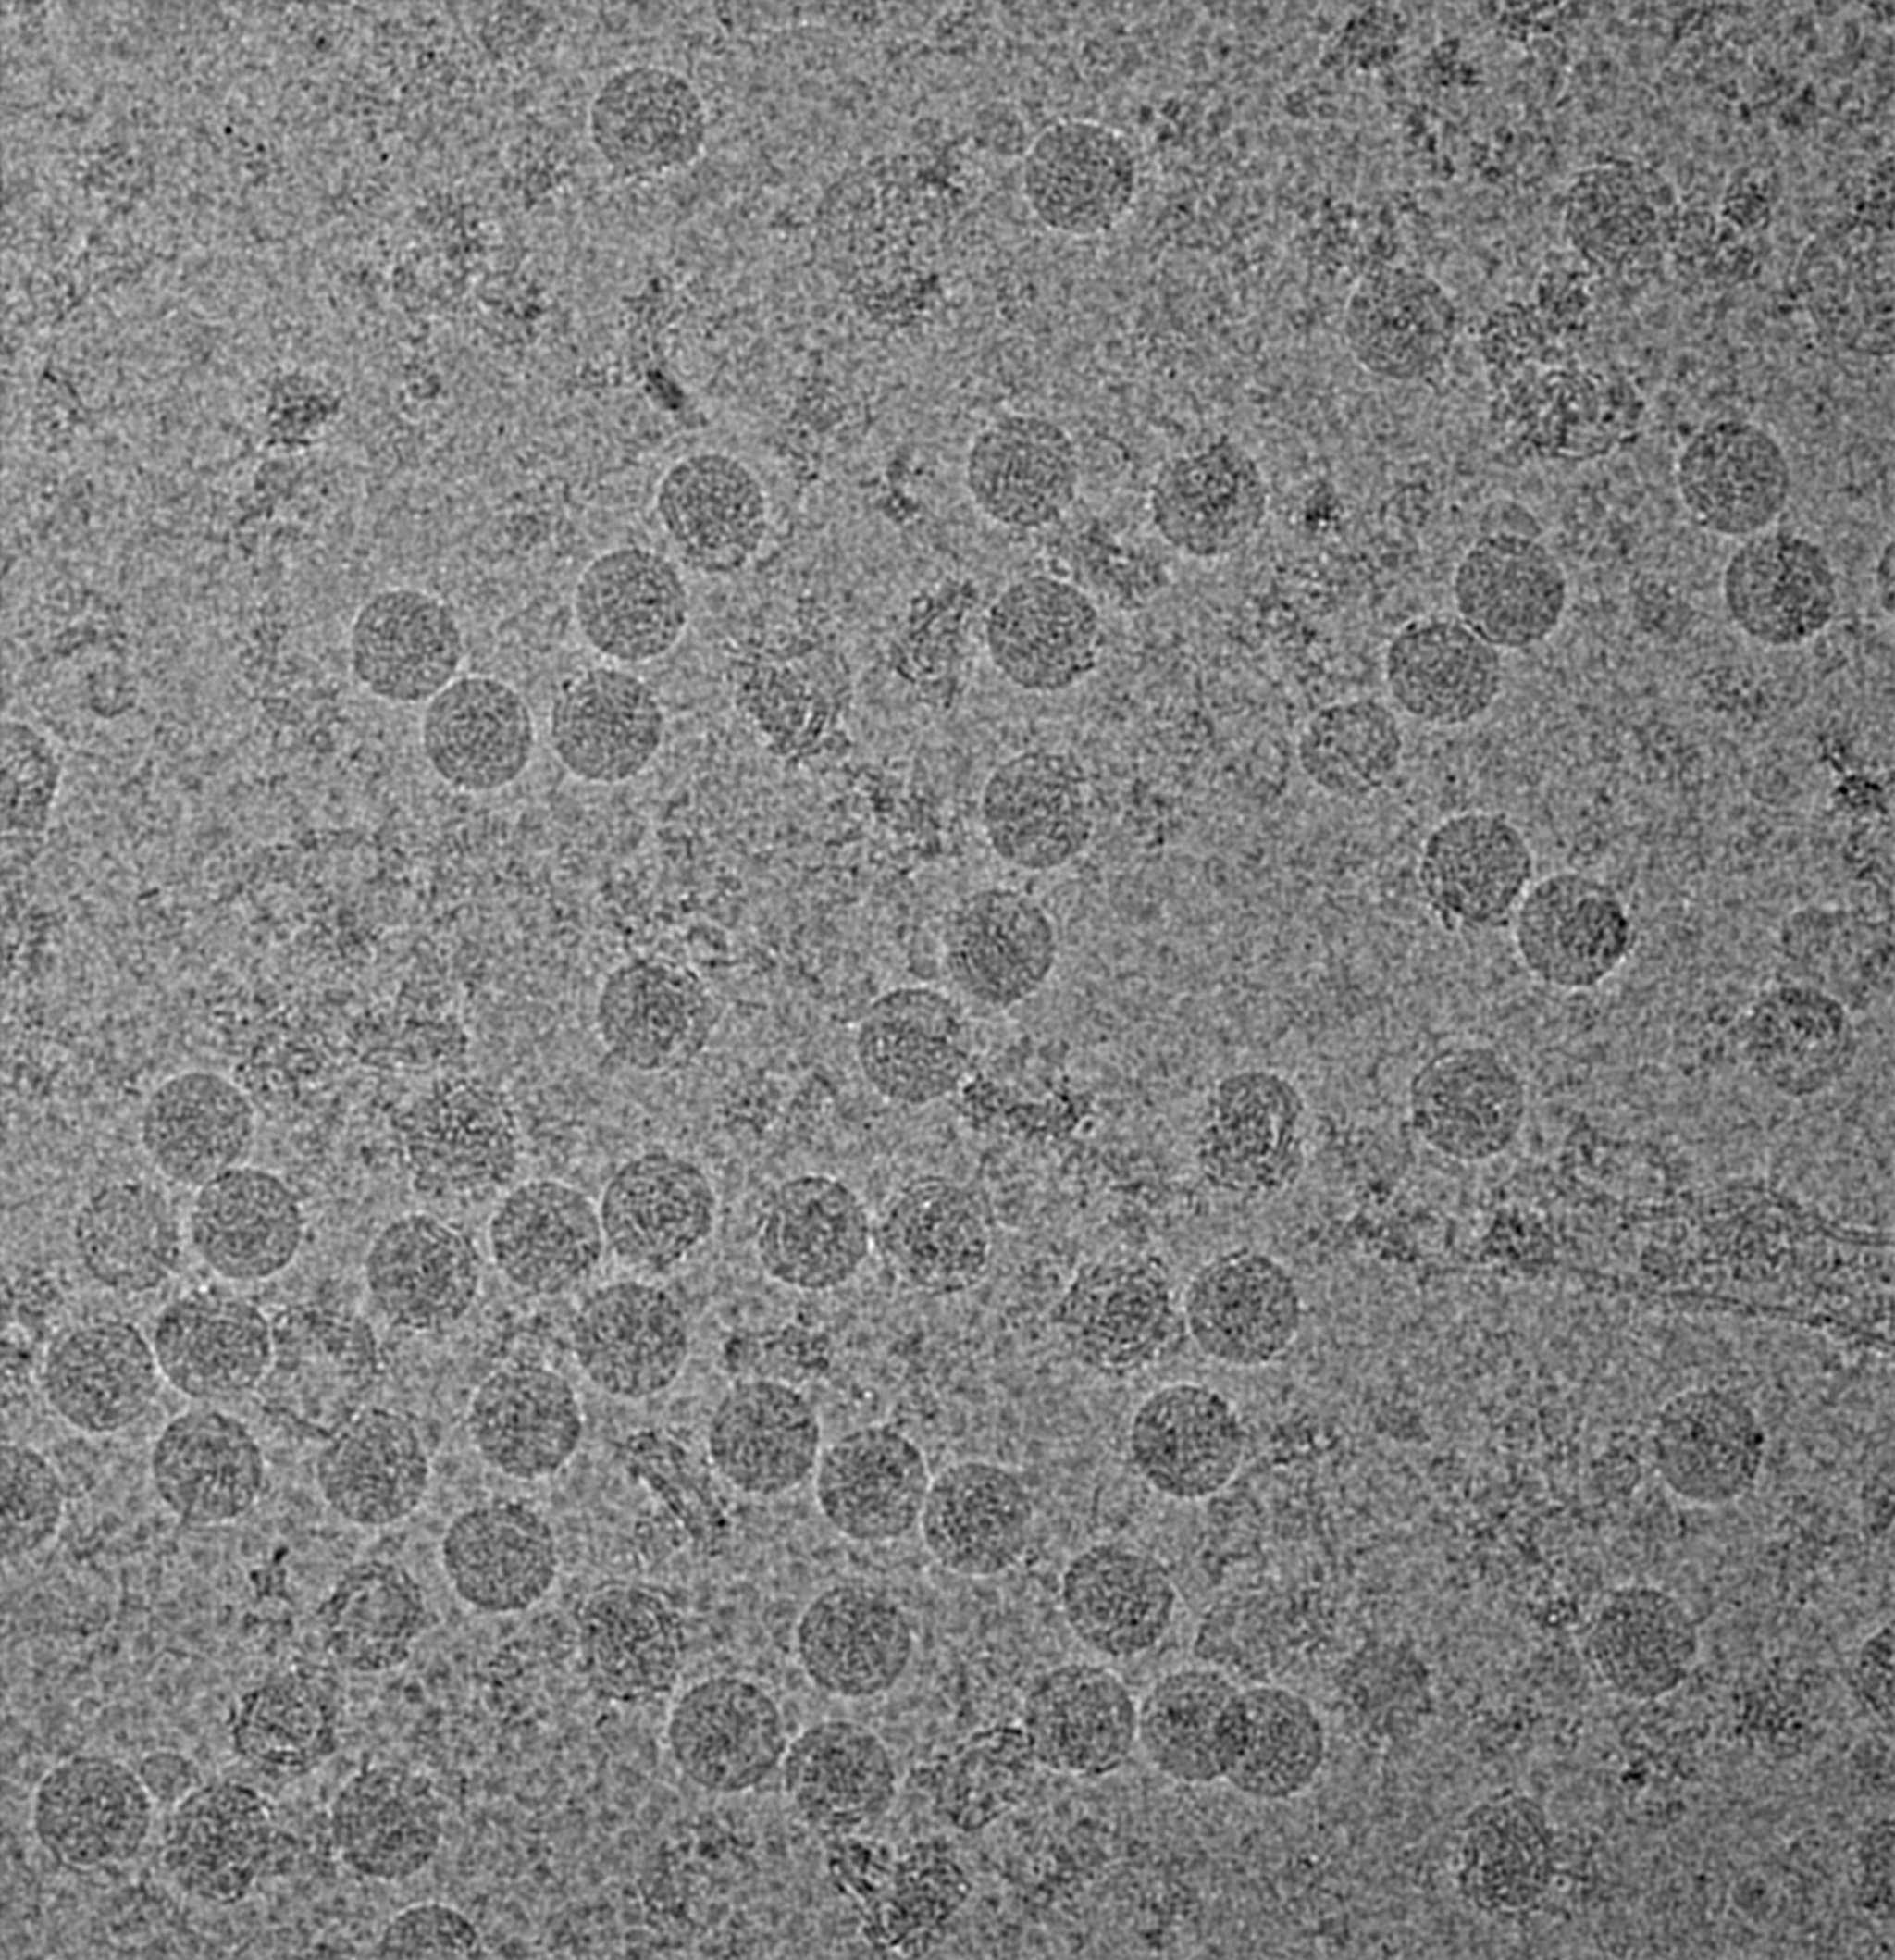

frozen zika virus

An image of the Zika virus using cryo-electron microscopy, in which the virus is first frozen then imaged. The dots are individual proteins. Purdue University image/courtesy of Kuhn and Rossmann research groups